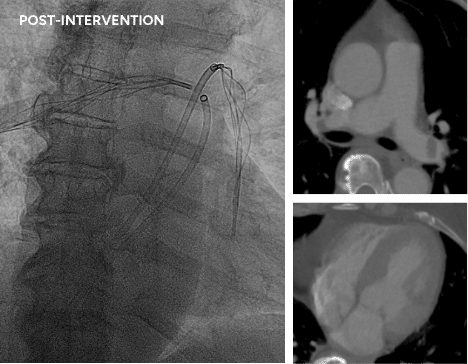

5.

Bilateral PE case

RESCUE protocol – total of 14mg r-tPA (7mg per lung)